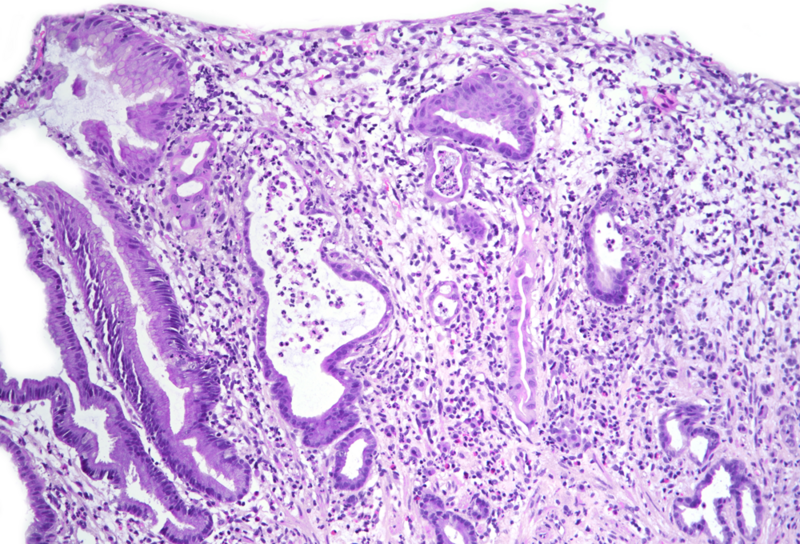

Gastric biopsies from a 68-year-old male with history of lung cancer.

Immune checkpoint inhibitor associated gastritis.

Histology showed an extremely altered gastric mucosa, with architectural distortion by glandular atrophy, degenerative epithelial changes, erosions and an expanded oedematous lamina propria (PANEL A-C). On higher magnification, the lamina propria contained a mixed inflammatory infiltrate, characterized by lymphocytes, plasma cells, eosinophils and neutrophils, focally with abscess formation. We observed withering glands lined by flattened eosinophilic epithelium, occasionally containing apoptotic debris (PANEL D-E); in other areas, little atrophic neuroendocrine nests were found (PANEL F). In summary, there was a severe acute inflammation and signs of acute epithelial injury highly suggestive of a drug-induced gastritis, consistent with injury due to pembrolizumab.